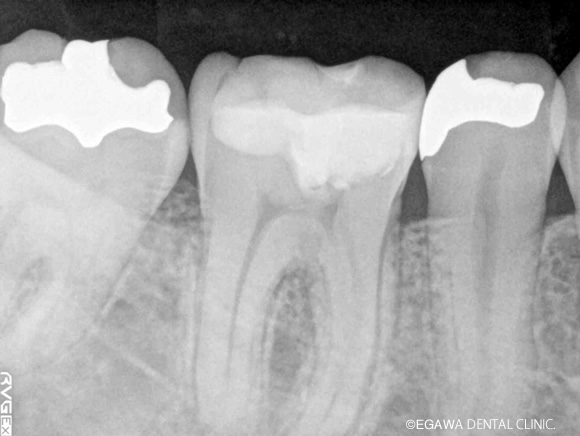

術前:レントゲン

術後:レントゲン

直接覆髄で歯髄を残せました(凹凸部分がMTAの箇所)

不幸にして歯髄治療を行わなければいけない場合、ファーストチョイスで直接覆髄を行いますが、直接覆髄でもダメなケースは根管治療を行います。まずは根管治療を行い、もし治らない場合は、根管治療は何度も続けるものではありません。その場合、後述でご紹介している歯根端切除術などの外科的な根管治療に移行します。その際、CTによる精密な診査・診断が必要となります。